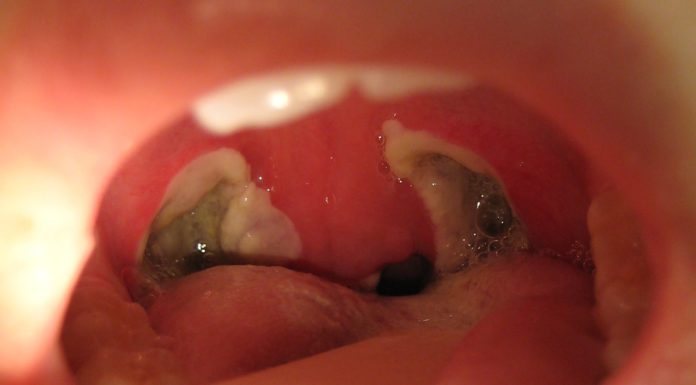

What Is a Tonsillectomy?

The tonsils may be removed due to repeated infections or enlargement that affects breathing.A tonsillectomy is surgery t